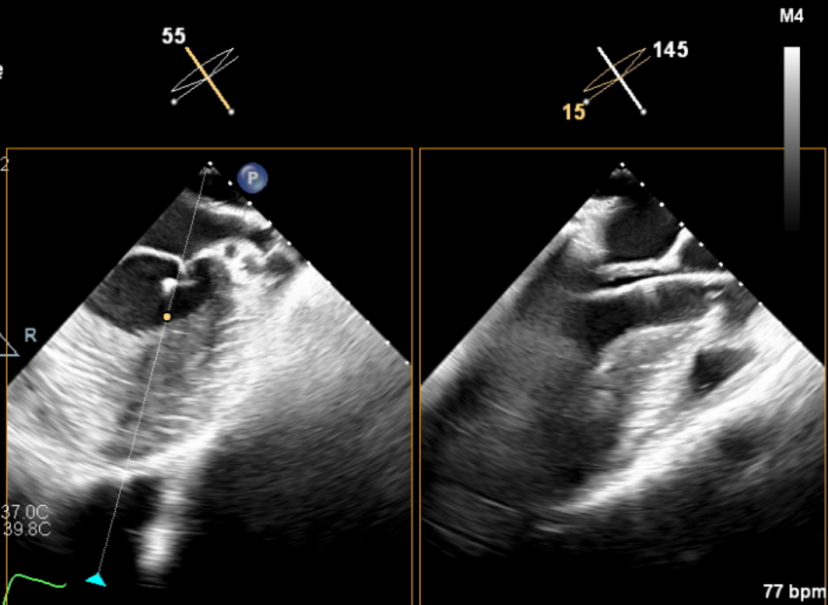

输送器顺利跨瓣,释放外鞘管,开始定位释放,超声评估可见定位件入窦可,后释放内鞘管,打开瓣架,瓣叶活动良好,无瓣周反流,综合考虑瓣膜稳定良好,脱钩释放。

(输送器跨瓣)

(瓣膜打开定位件)